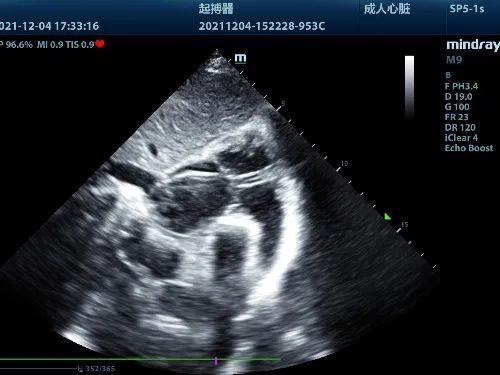

电极导线到位后通过彩超判断电极预留长度及三尖瓣反流情况,再进行缝合固定,最后连接起搏器缝合囊袋,手术顺利完成。术后患者症状明显改善,心率恢复正常状态。

右房电极预留长度